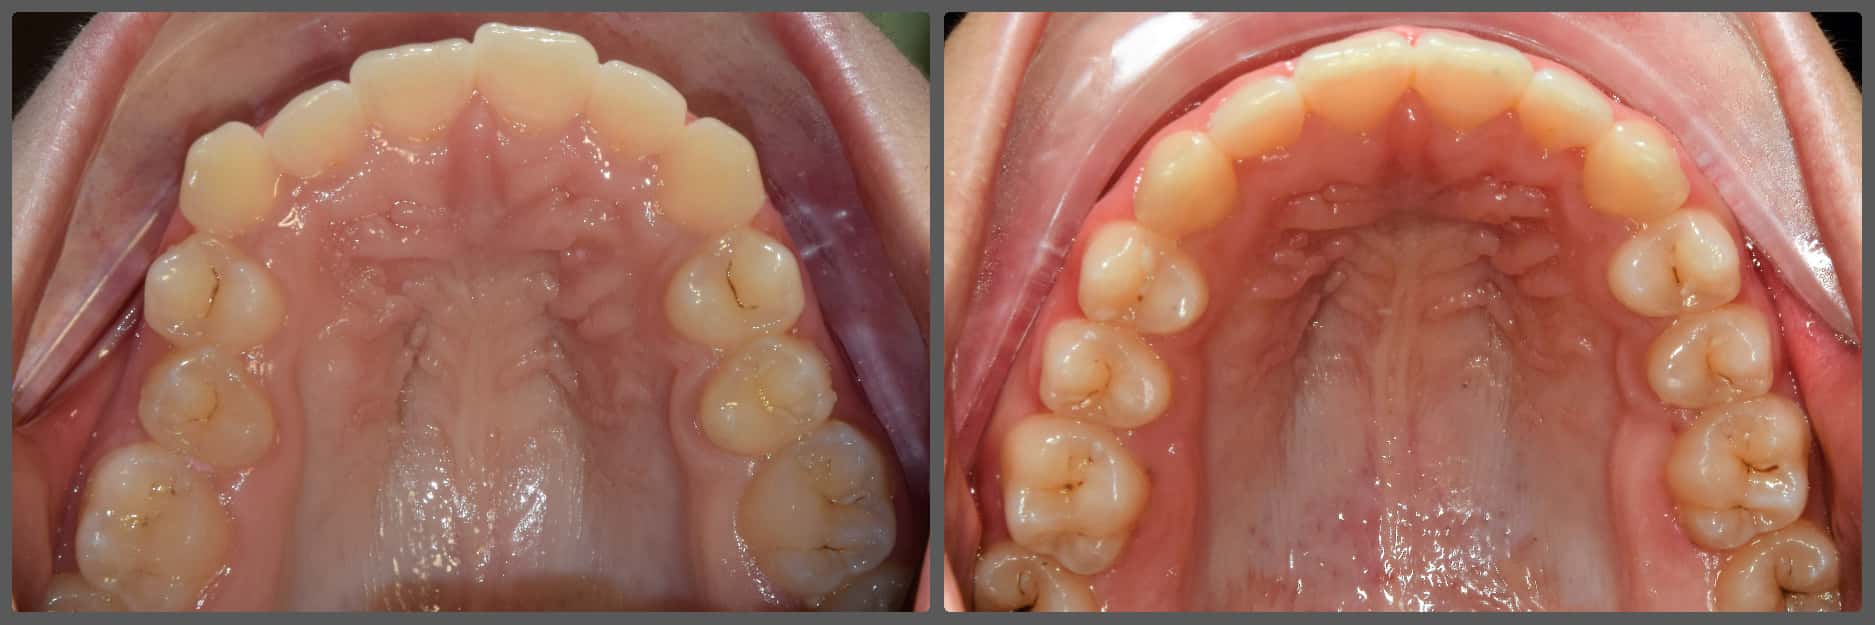

Extrém súlyos alsó-felső torlódása miatt jött hozzám fogszabályozási konzultációra Viki. A korábbi szakvélemények mindegyike foghúzással járt volna. Súlyosan eltolódott alsó-felső középvonalat, súlyos alsó-felső torlódást, mélyharapás, fogívszűkületet és a nyelv felé dőlő fogíveket diagnosztizáltam. Viki harapási és anatómiai adottságai miatt úgy ítéltem meg, hogy a kezelését foghúzás nélkül is végig tudjuk vinni. H4 önligírozó fogszabályzó készüléket ragasztottunk Vikinek, és a torlódott területeken tolórugóval csináltunk helyet a fogívből kiszorított fogaknak. A harapás harmonizálást és a mélyharapás korrekcióját intermaxilláris gumihúzással, valamint harapásemelőkkel végeztük. A teljes kezelés 26 hónapig tartott, melynek végére egy igazán gyönyörű, telt mosolyt sikerült Viki arcára varázsolni, mindemelett a szinte tökéletes oldalsó fogilleszkedést is megtartottuk, tovább javítottuk. Az ilyen látványos változások, páciens átalakulások miatt szeretem a legjobban a munkám!